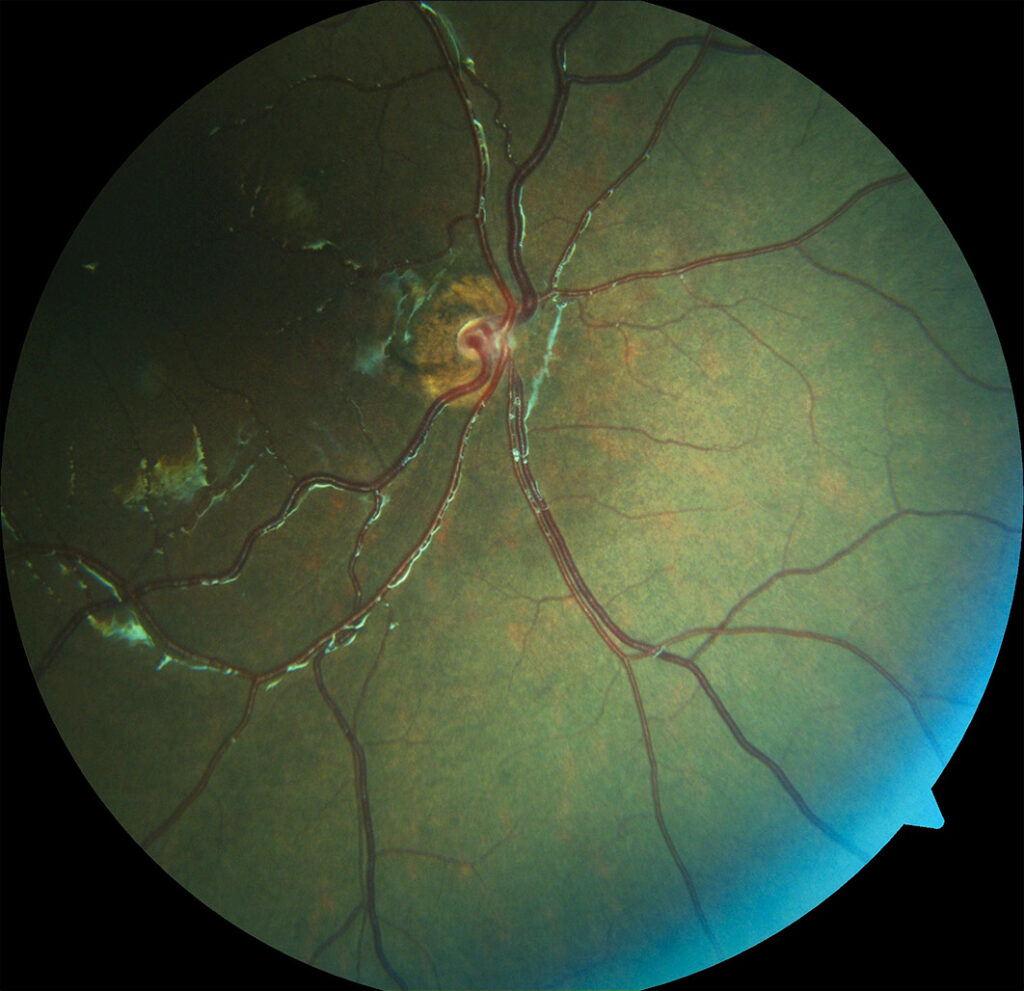

Retinitis por CMV – “Fields of Fire”

Hombre de 37 años con diagnóstico de SIDA, sin tratamiento antirretroviral previo. Recibía tratamiento sistémico por citomegalovirus, así como terapia dirigida a otras infecciones oportunistas, entre ellas, candidiasis esofágica.

La retinitis por citomegalovirus (CMV) es una infección ocular oportunista que afecta a pacientes con inmunosupresión severa. Se presenta en tres formas: fulminante, con necrosis hemorrágica y lesiones blancas o amarillas; granular, con lesiones granulares periféricas y poca necrosis; y perivascular, con angiítis en “rama escarchada” alrededor de los vasos retinianos. El diagnóstico se basa en la historia clínica, hallazgos en fondo de ojo y puede confirmarse con PCR. Es importante diferenciarla de la necrosis retiniana aguda (ARN), causada por virus herpes simplex o varicela-zóster, que afecta principalmente a pacientes inmunocompetentes o con inmunosupresión leve, y se caracteriza por necrosis rápida, vitritis, vasculitis y lesiones bien definidas.

El paciente presentó retinitis por citomegalovirus, en forma fulminante, con afectación macular demostrada por OCT. Fue tratado con terapia sistémica e inyecciones intravítreas de ganciclovir, logrando una respuesta clínica favorable. Actualmente, su agudeza visual es de 20/30.